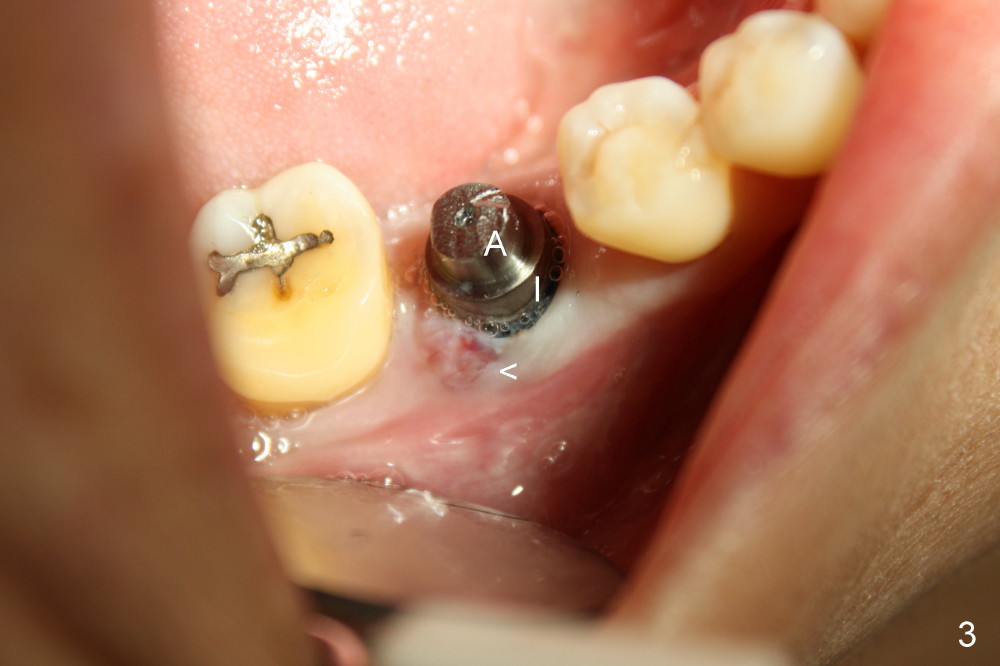

A gingiva-level implant (Fig.1 I) is placed immediately in the extraction site of the tooth #30 (*: remaining mesial and distal sockets after implantation). There appears to be no bone growth in the sockets 4 month postop (Fig.2), although the implant is stable. Clinically there is sign of infection (Fig.3 <) distobuccal to the implant (I). Since the patient is asymptomatic, it feels that the infection may resolve by itself. The abutment (A) is placed and impression is taken. Fourteen days later, the infection remains (Fig.4) after seating the permanent crown.